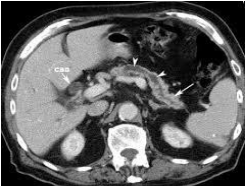

- Sỏi tụy: chụp cắt lớp vi tính là biện pháp tốt nhất để xác định sỏi tụy. Sỏi kích thước trên 1mm có thể thấy thấy trên phim chụp CLVT, sỏi xuất hiện trong nhu mô hoặc trong ống tụy hoặc ở cả nhu mô tụy và ống tụy.

- Giãn ống tụy chính: ống tụy có thể nhìn thấy khi đường kính > 3mm trên phim chụp với các lớp cắt mỏng. Nét đặc trưng của giãn ống tụy trong VTM là giãn không đều, có nhiều đoạn hẹp xen kẽ các đoạn giãn, tạo hình ảnh như tràng hạt.

- Nang giả tụy: biểu hiện bởi những cấu trúc giảm tỷ trọng (0-20HU), ranh giới rõ, nằm trong nhu mô tụy hoặc các vị trí ngoài tụy, không ngấm thuốc sau tiêm. Nếu Nang giả tụy có biến chứng Chảy máu trong nang hoặc nang bị bội nhiễm thì tỷ trọng trong nang có thể cao hơn.

- Hẹp đường mật chính đoạn trong tụy: khi quá trình viêm tập chung ở đầu tụy, tổ chức xơ tăng sinh gây chèn ép làm hẹp đoạn ống mật chủ trong tụy, và gây giãn đường mật trên chỗ hẹp.

- Các tổn thương mạch máu: Huyết khối tĩnh mạch lách, tĩnh mạch mạc treo tràng trên, Huyết khối tĩnh mạch cửa, thường kết hợp với các dấu hiệu tăng áp lực tĩnh mạch cửa. Giả phình động mạch hay gặp giả phình động mạch lách, biểu hiện của khối giả phình mạch là tỷ trọng ngang tỷ trọng mạch máu ở thì động mạch.